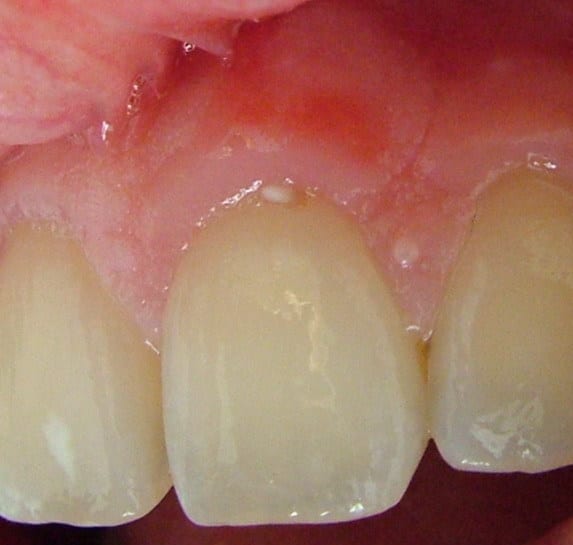

effectivement en augmentant les contrastes, la cicatrice est vilaine...

... même le frein médian a été sectionné ... par PhotoShop ;-)

c'est à la vertical ou à l'horizontal ? j'vois rien sur la photo d'ivetol... c'est pas encore un canular au moins ??

Voilà, je viens de reprendre 2 clichés plus nets.

Merci pour les réponses.

Au collet de 21 ce n'est pas du pus mais un petit morceau de composite flow .( que je me suis empressé d'enlever après la photo).